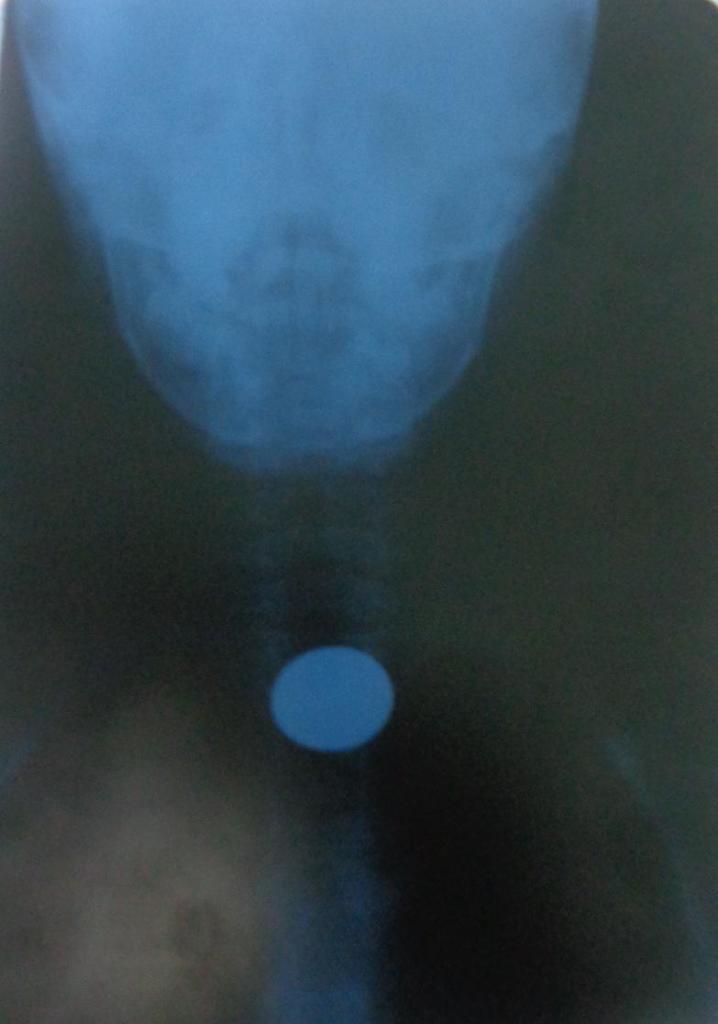

“Pero el peligro mayor se concentra en los cuerpos extraños bronquiales con tres estadios básicos: cuando el paciente siente que se asfixia, hace un cuadro aparatoso de tos y se pone cianótico: ahí puede ser que fallezca ante la imposibilidad de respirar, o bien que expulse el objeto, o que desafortunadamente este vaya hacia uno de los bronquios.

“He ahí la etapa crítica, señala enfático el doctor Francisco Macías Fonseca, profesor auxiliar de Otorrinolaringología, la familia no puede pensar que llegó la calma y todo pasó, por el contrario, es ese el momento crucial, en el que con más premura hay que acudir al médico, principalmente si se trata de semillas: frijoles, maíz, maní, mamoncillo, tamarindo, anón…

“Si dejan al pequeño en casa sobreviene inevitablemente una neumonía, o un enfisema (aire en el pulmón), una atelectasia (colapso del pulmón por falta de aire), o absceso pulmonar, y tristemente la muerte”.